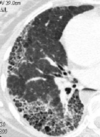

Estudios de imagen para Enfermedad Pulmonar Infiltrativa Difusa Crónica

RX * Poco específica * Patrón intersticial bibasal TC * Diagnóstico de NIU * “Patrón en panal” * Bronquiectasias por tracción en las bases (dilatación bronquial)

80

Patrón en panal

81

Patrón intersticial bibasal

82